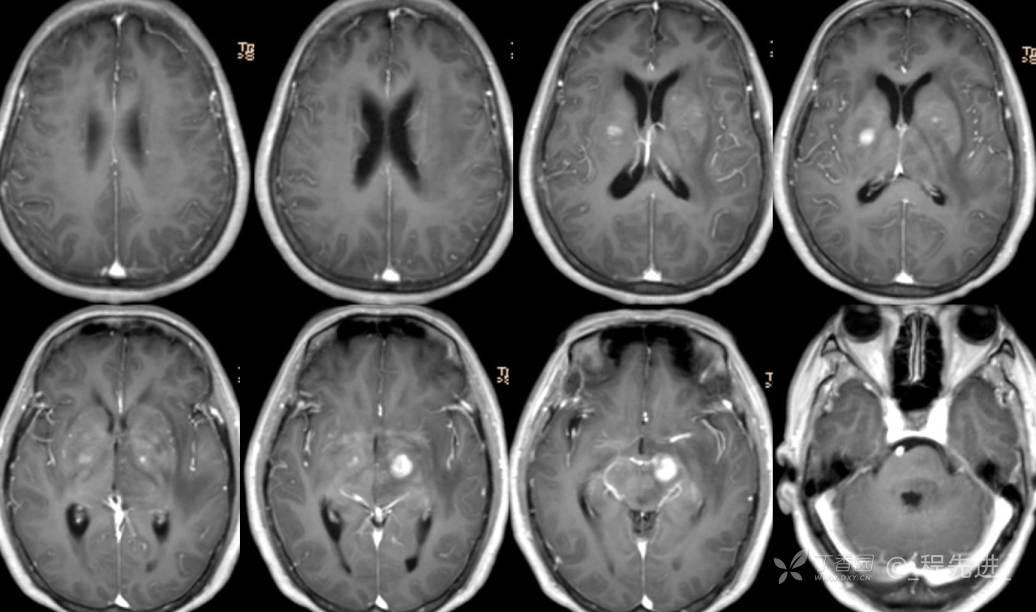

2月特别精彩病例|头晕伴言语含糊1月,梅毒患者的颅内占位你如何考虑?【病理已公布】

主诉:头晕伴言语含糊1月。

梅毒TRUST血清实验(TRUST):1:32阳性(+)

梅毒特异性抗体凝集试验(TPPA):阳性 (+)